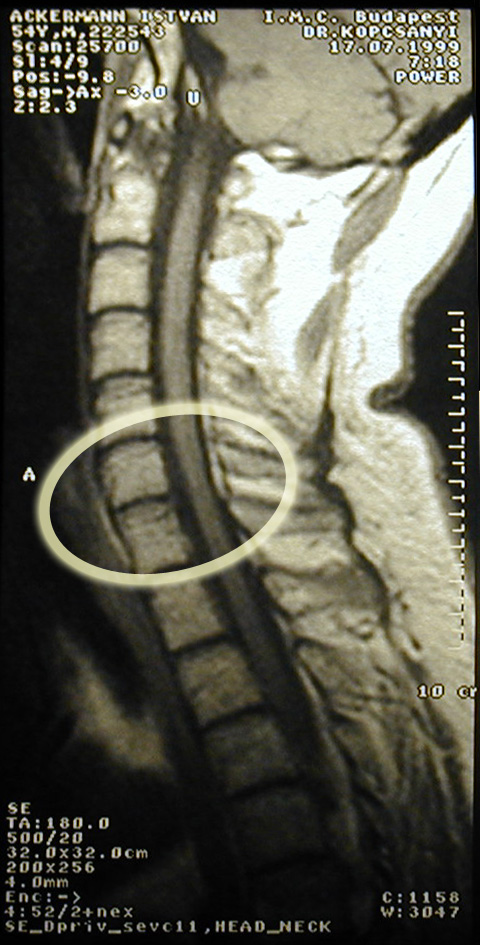

Gerincsérv

(az 5-ös és 6-os nyaki csigolya között)